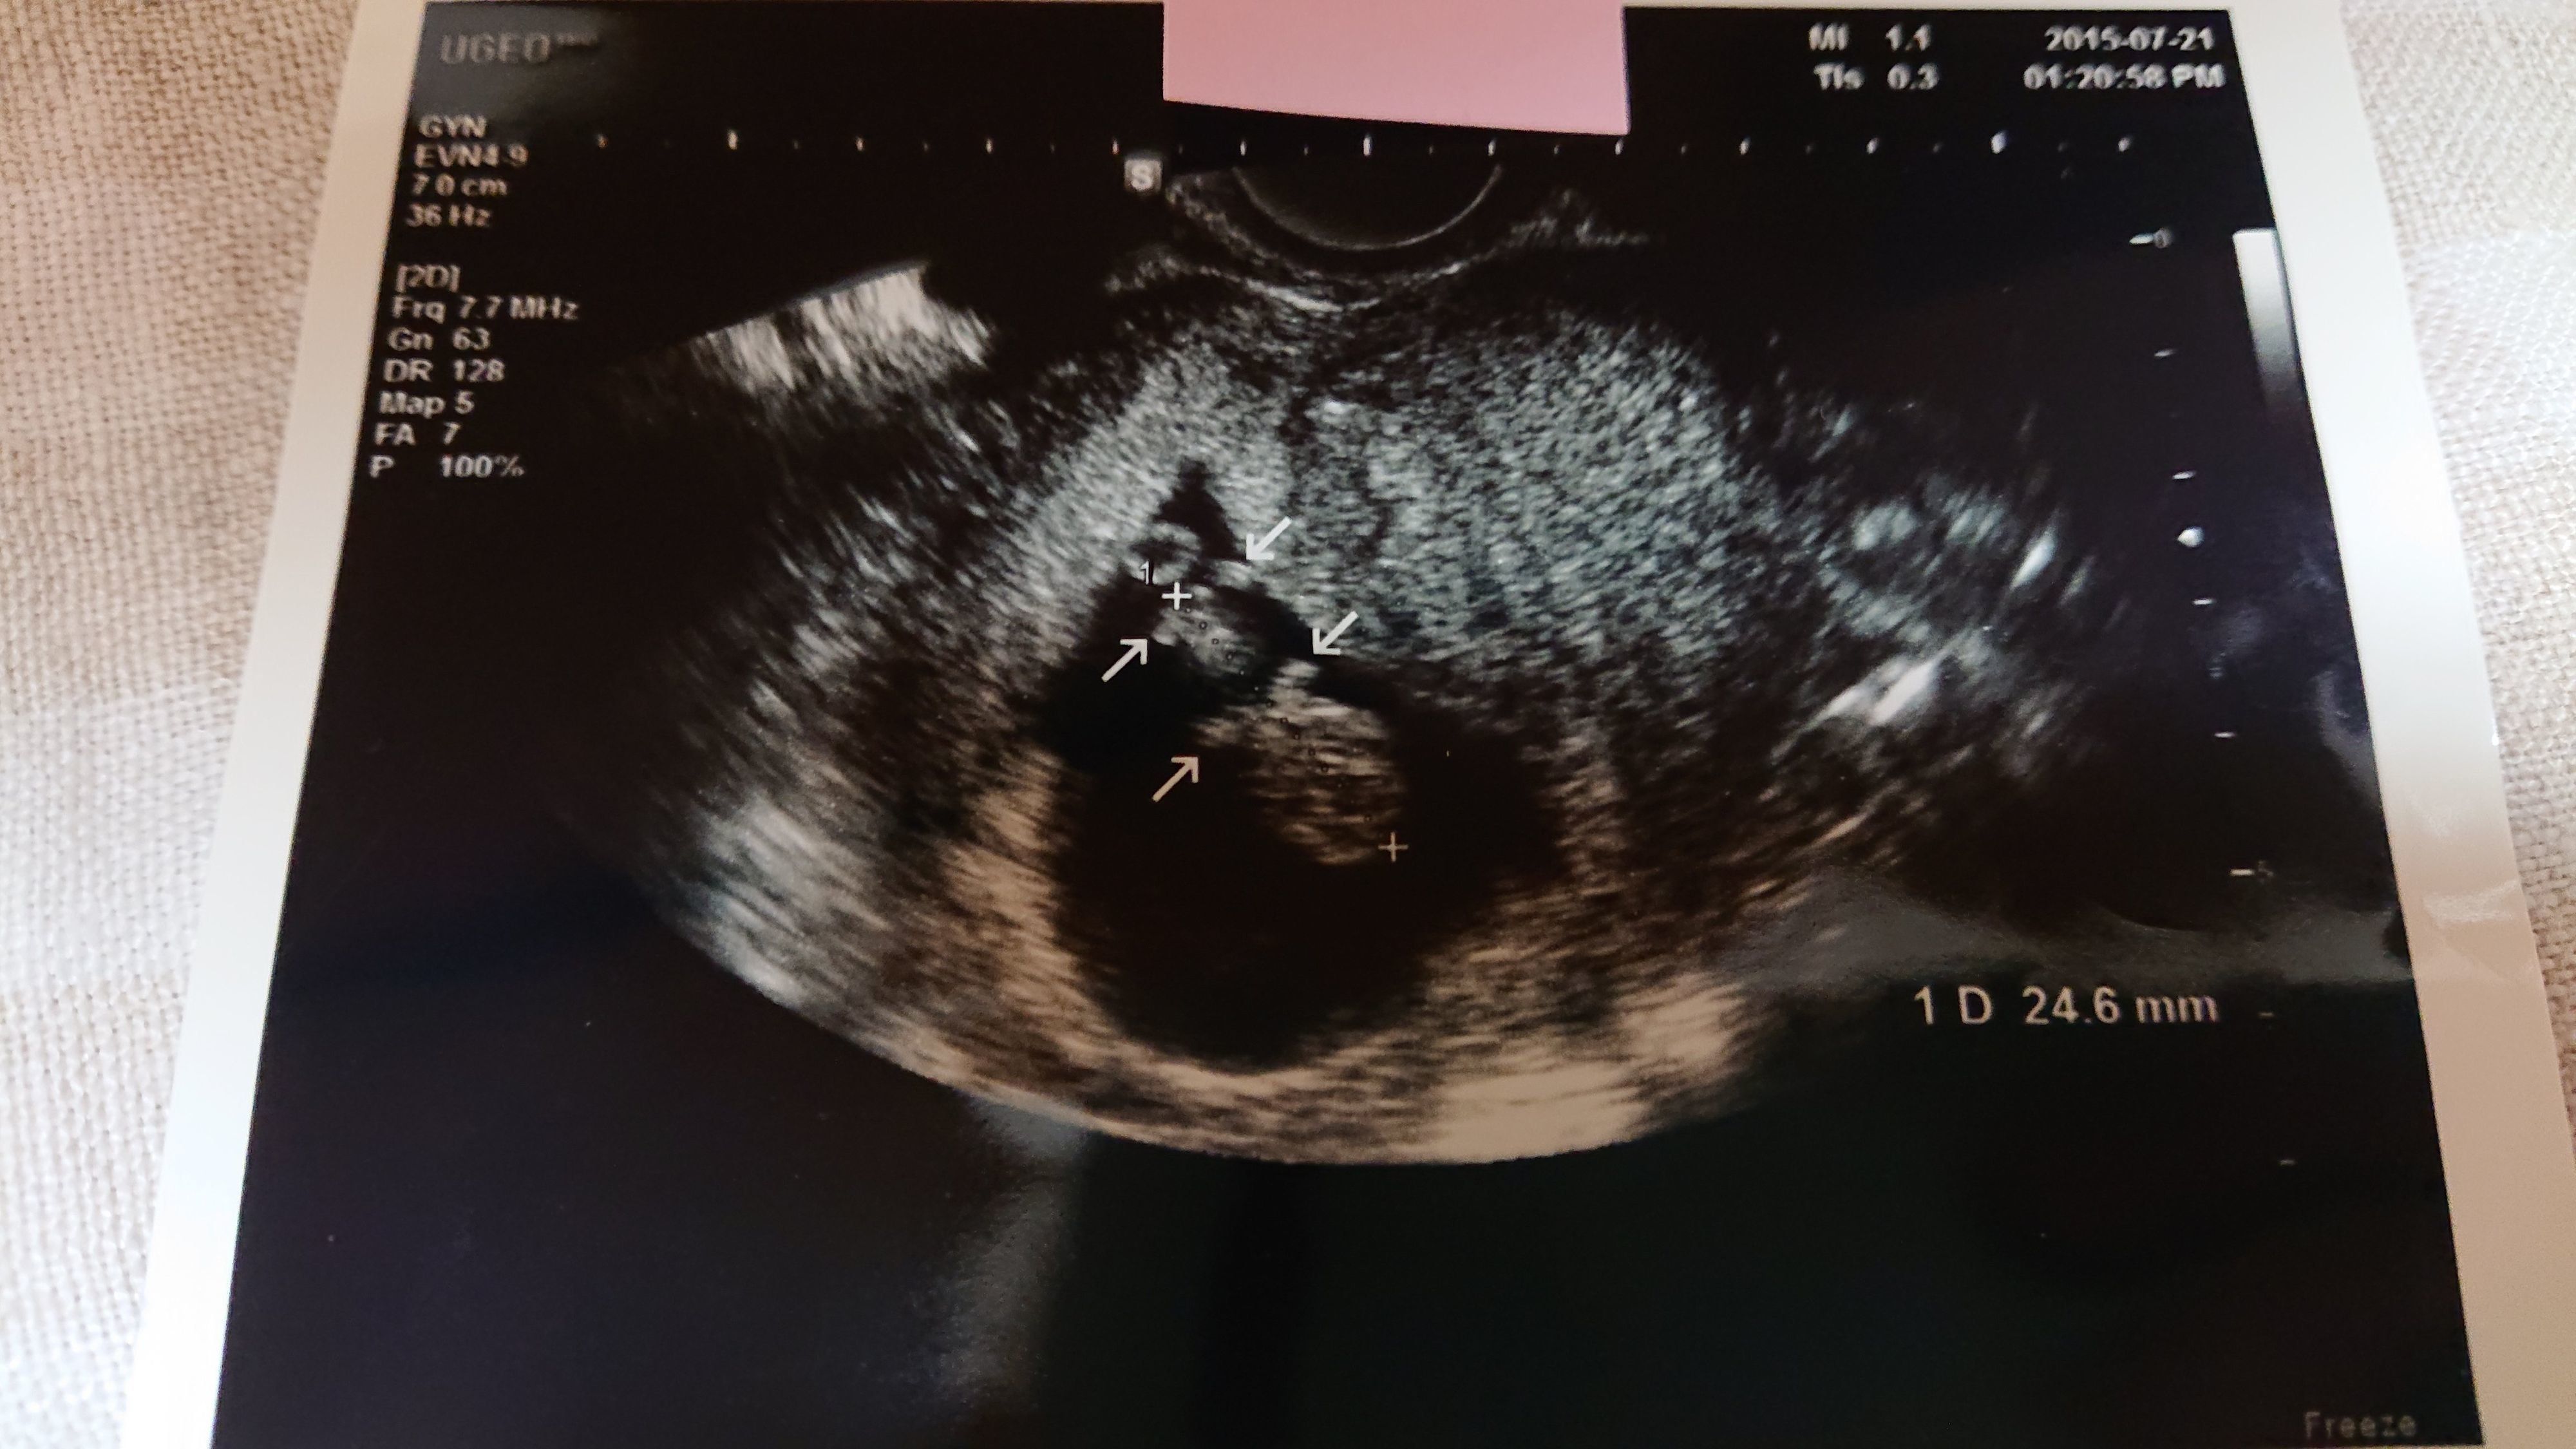

《妊娠5週目のエコー写真》

初めてのエコー検査からちょうど1週間後、赤ちゃんがおなかにやってきてくれたか、再度、確認する日がやってきました。まだ、赤ちゃんの姿は見えないけれど、胎嚢という赤ちゃんが育つためのお部屋が出来ているのを確認できました。胎嚢はエコー写真の黒丸部分です。私自身、「自分の体は妊娠できるのか」と長年不安だったので、前回は何も写っていなかったエコー写真を見たときは不安でしたが、今回は、くっきりと赤ちゃんのお部屋である胎嚢を見つけることができ、感動しました。